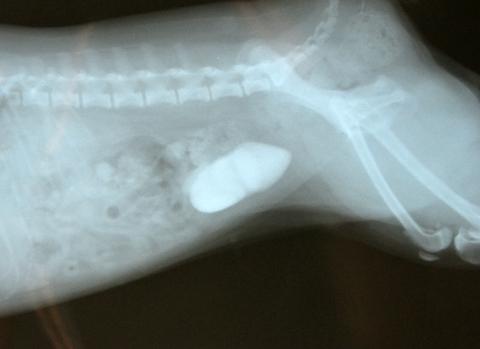

Мочекаменная у собаки симптомы лечение

Мочекаменная у собаки симптомы лечение 109 фотографий